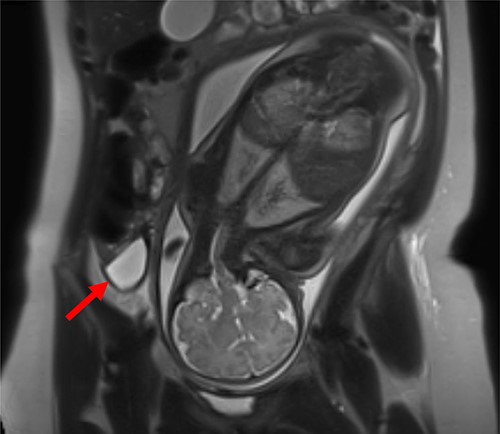

Patient 1 (31 years, 35 + 4 weeks of pregnancy) was suffering colicky pain in the right lower quadrant accompanied by symptoms of nausea, emesis, and an episode of diarrhea since the night before. Clinical examination revealed strong pain with guarding upon palpation of the right lower abdomen. Blood tests showed no abnormalities. Pregnancy-related causes were excluded by gynecological examination; cardiotocography and fetal ultrasonography were both physiological. An urinary infection was suspected, so the patient was hospitalized and intravenous antibiotic treatment (co-amoxicillin) initiated. Two days after admission, an MRI revealed a fluid collection in the right lower abdomen. The appendix could not be delineated clearly (Fig. 1).

MRI of patient 1 revealing a fluid collection in the right lower abdomen.

On the fourth day after admission, serum CRP level rose to 66.8 mg/l. Follow-up ultrasonography detected a mass in the right lower abdomen, suggestive of an abscess. An interdisciplinary decision was made in favor of surgical exploration under prophylactic perioperative tocolysis with Atosiban. Midabdominal horizontal right-sided laparotomy was performed, showing torsion and necrosis of the right ovary and hemorrhagic ascites. The appendix appeared reddened and thickened. The ovary was removed, and incidental appendectomy performed. Histology showed hemorrhagic infarction of the ovary and fallopian tube and a normal appendix. The patient showed a small bowel paralysis, but recovered quickly and was discharged 1 week after surgery without complications for the infant.